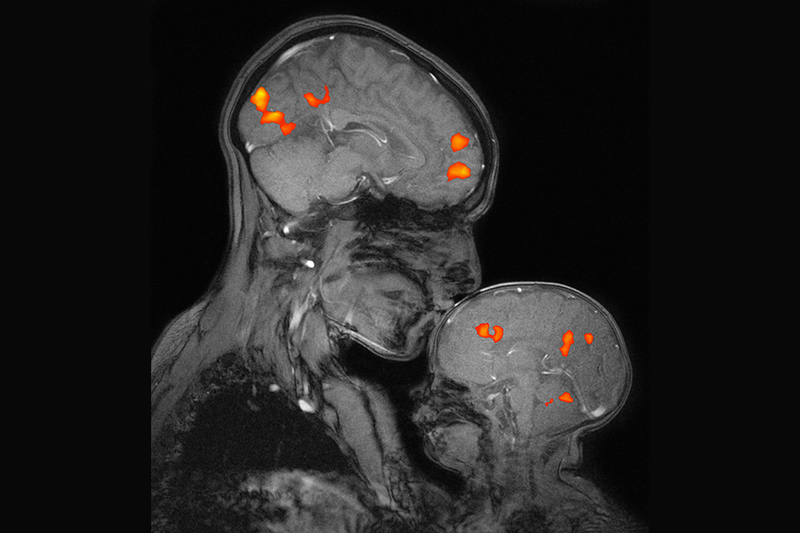

Desimone highlighted the institute’s recent discoveries, including the development of the CRISPR genome-editing system, which has culminated in the world’s first CRISPR gene therapy approved for humans — a remarkable achievement that is ushering in a new era of transformative medicine. In other milestones, McGovern researchers developed the first prosthetic limb fully controlled by the body’s nervous system; a flexible probe that taps into gut-brain communication; an expansion microscopy technique that paves the way for biology labs around the world to perform nanoscale imaging; and advanced computational models that demonstrate how we see, hear, use language, and even think about what others are thinking. Equally transformative has been the McGovern Institute’s work in neuroimaging, uncovering the architecture of human thought and establishing markers that signal the early emergence of mental illness, before symptoms even appear.